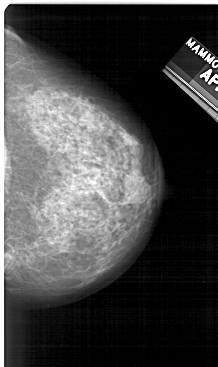

A_1279_1.RIGHT_MLO

RIGHT_MLO LINES 5491 PIXELS_PER_LINE 2926 BITS_PER_PIXEL 12 RESOLUTION 43.5 NON_OVERLAY